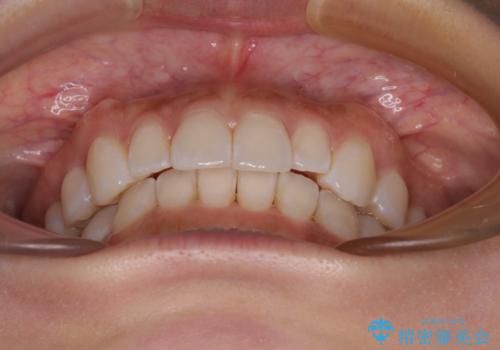

【モニター】前歯のデコボコと小さい前歯 インビザライン矯正とオールセラミッククラウン補綴治療

上下前歯の歯列不正はインビザラインにより整え、その後に、矮小歯の前歯をオーダーメイドタイプのオールセラミッククラウンにて補綴治療することとしました。

インビザライン矯正の場合、矮小歯を矯正治療後にセラミックとするかどうかを矯正治療開始前に決める必要があるため、悩んでしまう方が多いです。

セラミッククラウンにて大きさを変更することを前提に矯正治療を開始したため、大変満足のいく仕上がりとなりました。